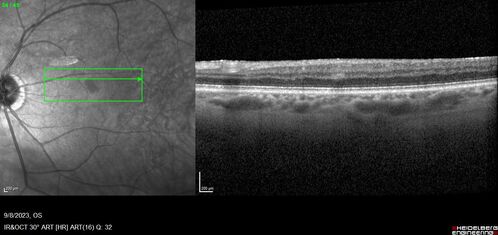

Paracentral acute middle maculopathy - isolated

83 year old man New spot in the vision yesterday left eye.

Medical Hx: Pure Hypercholesterolemia

Systemic Meds: Crestor.

VA OD: Dcc20/20

VA OS: Dcc20/20

IOP: TP: OD:19 OS:10

Isolated PAMM lesion